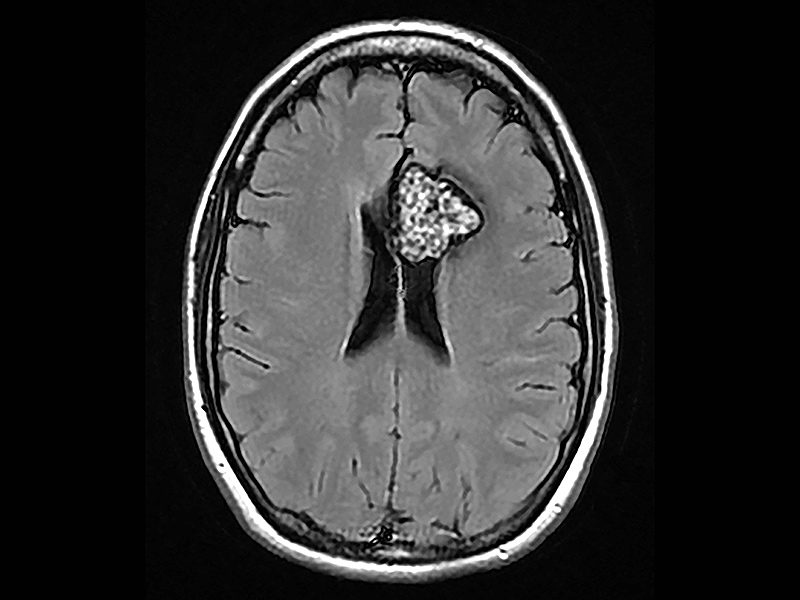

脑海绵状血管瘤

脑海绵状血管瘤出血的病因

脑海绵状血管瘤(CCM)是常见的血管畸形,患病率为0.2%-0.5%。由于其高达60%的年出血率,CCM可能具有相当大的临床影响。脑海绵状血管瘤出血的原因有哪些?Jeon等对成人Zabramski I - III型...

脑海绵状血管瘤什么情况下会出血?

脑海绵状血管瘤是一种常见的血管畸形,通常无症状且偶然发现。然而,在相对少见的出血事件中,患者可能会出现癫痫、头痛或局灶性神经功能障碍。大多数病变是散发性的;然而,如...

脑海绵状血管瘤遗传模式详解:对家庭成员的风险

脑海绵状血管瘤 是大脑和脊髓的血管畸形。脑海绵状血管瘤的直径从几毫米到几厘米不等。脑海绵状血管瘤随着时间的推移在大小和数量上增加或减少。根据患者的年龄、脑成像的质量...

脑海绵状血管瘤 是脑血管疾病的一种,是一种良性血管性脑瘤。脑海绵状血管瘤实际并不是肿瘤,而是血管畸形。大多数患者在接受脑部核磁共振成像(MRI)检查时,才知道自己患有这种...